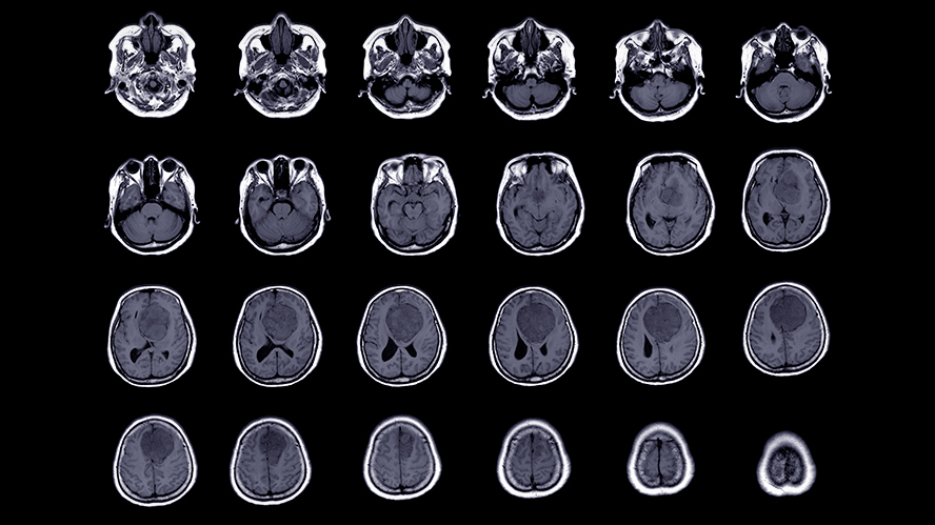

Clinicians have long faced these issues when grading meningiomas, tumours that come from the membranes that surround the brain and spinal cord (called the meninges). In a new study from UHN’s Princess Margaret Cancer Centre (PM), researchers may have found a way to resolve this issue and make grading meningiomas significantly more reliable. The team, led by Drs. Gelareh Zadeh and Farshad Nassiri, an Affiliate Scientist and Scientist, respectively, at PM, found that meningiomas with certain chromosomal changes called copy number alterations (CNAs)—in particular a 1p loss (a loss of the first half of chromosome 1) or 1q gain (a copy gain in the latter half of chromosome 1)— behave more aggressively than their grade would predict. As a result, these tumours may not be receiving the best treatment, negatively impacting patient outcomes.

This work highlights the critical need to improve the WHO grading system for CNS tumours like meningiomas, such as by incorporating genetic features like CNAs into grading criteria. Because meningiomas are one of the most common types of brain cancer in adults, rectifying the inconsistency in the current system could significantly improve care for a large population of patients with a challenging diagnosis and offer more patients a better chance at life after meningioma.